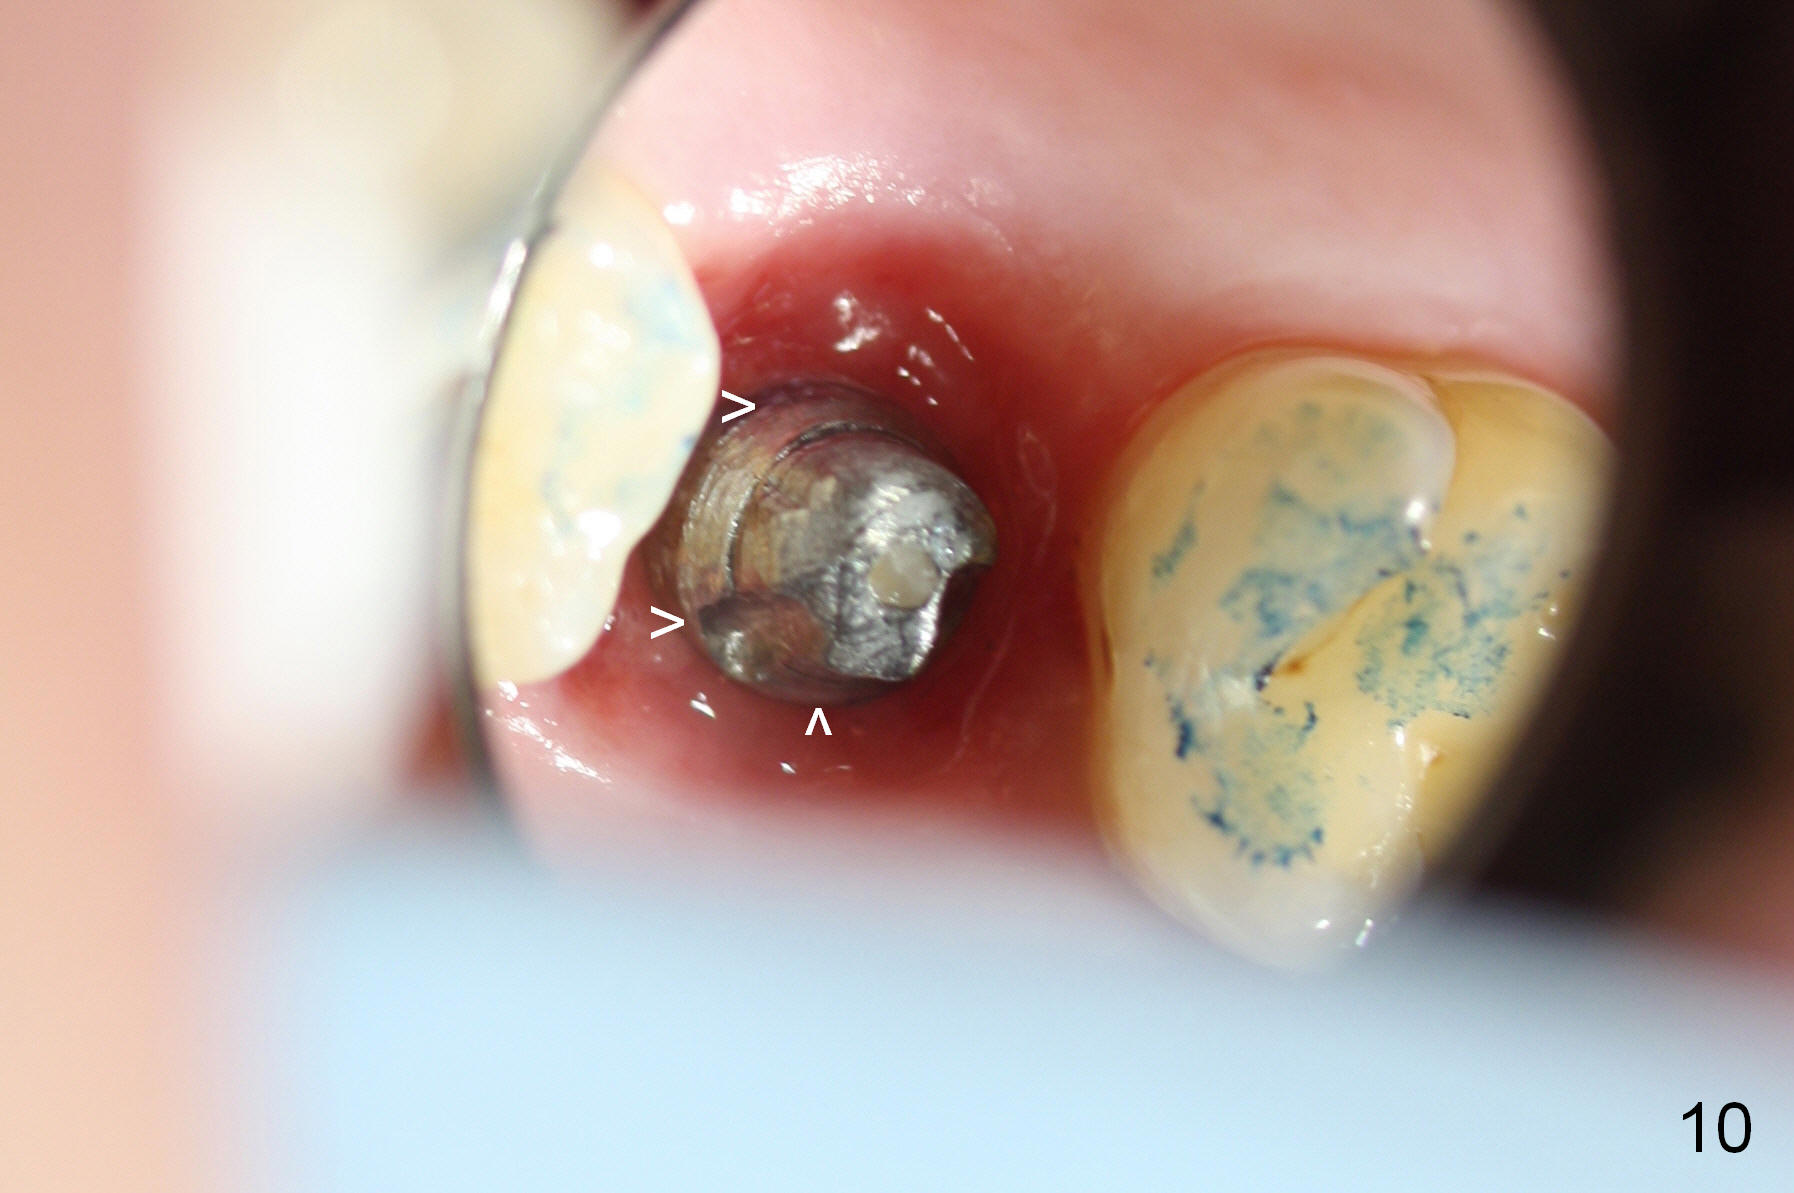

The implant remains stable 2.5 months postop without abnormal bone resorption (Fig.9). Since the provisional has dislodged on several occasions, impression is taken for final restoration. When the provisional is removed 3 months postop, the margin of the restoration is shown to be subgingival (Fig.10 arrowheads), but is distinctly separated from the gingiva. This is due to the presence of the provisional (its margin were fabricated slightly deeper). The provisional is also intentionally fabricated slightly larger than the final restoration. When the latter is cemented, there is space to remove extra cement trapped subgingivally (Fig.11). No cement is visible post cementation (Fig.12 (C: crown)). Eighteen months post cementation, the patient returns for recementation. After laser gingivectomy and Panavia resin bonding, PA shows residual cement (Fig.13 ^). After repeated removal with Piezo scaler and explorer, the residual cement appears to be smaller, which is ignored at the time of X-ray taking (Fig.14 ^). More dismayed is tight mesial contact. Water pik is recommended. When peri-implantitis develops later on, make an incision for cement removal. If the crown is dislodged soon, check whether the existing abutment is loose, remove acrylic in the access hole and remove the abutment. Install a new 4x3 mm one. Trim the abutment carefully and more on the opposing tooth.